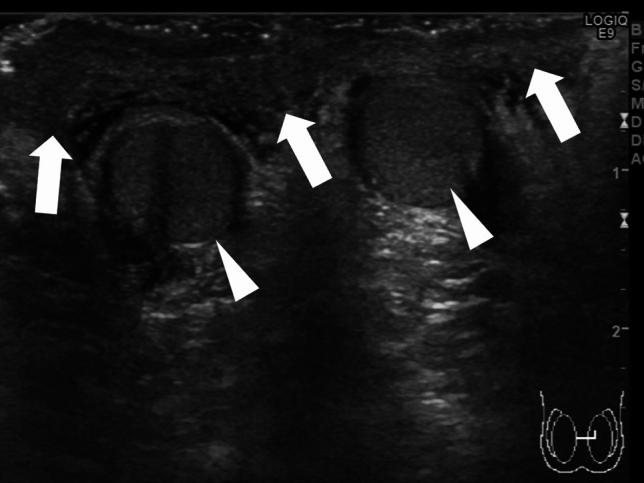

Testicular torsion is a urological emergency caused by the loss of testicular tissue due to ischemic damage. Rapid diagnosis and urgent treatment play a crucial role in the management of testicular torsion. Manual detorsion can be performed at the bedside, thereby reducing the duration of ischemia. Recent studies have reported the use of point-of-care ultrasonography for diagnosing testicular torsion; however, no review article has focused on the ultrasonographic findings pertaining to manual detorsion. This review describes the diagnosis of testicular torsion and the ultrasonographic indications for manual detorsion. Spermatic cord twisting or the whirlpool sign, absence of or decreased blood flow within the affected testis, abnormal testicular axis, abnormal echogenicity, and enlargement of the affected testis and epididymis due to ischemia are the sonographic findings associated with testicular torsion. The following findings are considered indications for manual detorsion: direction of testicular torsion, i.e., inner or outer direction (ultrasonographic accuracy of 70%), and the degree of spermatic cord twist. The following sonographic findings are used to determine whether the treatment was successful: presence of the whirlpool sign and the degree and extent of perfusion of the affected testis. Misdiagnosis of the direction of manual detorsion, a high degree of spermatic cord twisting and insufficient detorsion, testicular compartment syndrome, and testicular necrosis were found to result in treatment failure. The success of manual detorsion is determined based on the symptoms and sonographic findings. Subsequent surgical exploration is recommended in all cases, regardless of the success of manual detorsion.

睾丸扭转是一种泌尿外科急症,由缺血性损伤导致睾丸组织丧失引起。快速诊断和紧急治疗在睾丸扭转的管理中起着至关重要的作用。床边手动复位可减少缺血持续时间。最近的研究报告了使用即时超声检查来诊断睾丸扭转,但没有综述文章专门关注手动复位的超声表现。本文描述了睾丸扭转的诊断和手动复位的超声指征。精索扭曲或漩涡征、受累睾丸内无血流或血流减少、睾丸轴异常、回声异常以及缺血引起的受累睾丸和附睾增大是与睾丸扭转相关的超声表现。以下发现被认为是手动复位的指征:睾丸扭转的方向,即内旋或外旋(超声准确性为 70%)和精索扭转的程度。以下超声表现用于确定治疗是否成功:漩涡征的存在以及受累睾丸的灌注程度和范围。手动复位方向的误诊、精索扭转程度高和复位不足、睾丸间隔综合征和睾丸坏死均导致治疗失败。手动复位的成功与否取决于症状和超声表现。无论手动复位是否成功,都建议进行后续的手术探查。